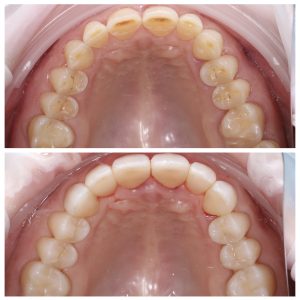

Visų dantų plombavimas dėl amžinių pokyčių ir bruksizmo

Šiuo atveju anksčiau pastebėjus dantų nudilimus, kuriuos lėmė amžius ir bruksizmas, ir anksčiau pradėjus nešioti apsauginę kapą (dantų kapa miegui), dantų nudilimai galėtų būti mažesni.

• Stiprus visų dantų nudilimas (priežastys – amžiniai pokyčiai ir bruksizmas);

Kompleksinis dantų gydymas apėmė šiuos etapus:

Visų dantų plombavimas prieš ir po Nudilusių dantų estetinis plombavimas prieš ir poVisų nudilusių dantų plombavimas prieš ir poViršutinis dantų lankas prieš ir po plombavimoApatinis dantų lankas prieš ir po plombavimo